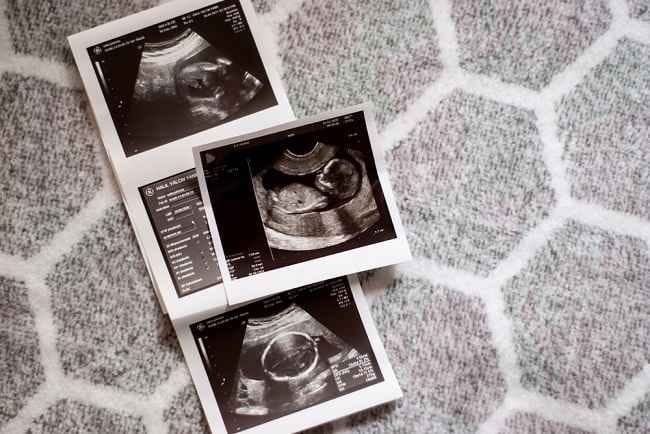

USG kehamilan merupakan salah satu cara untuk mengetahui perkembangan janin. Namun, banyak ibu hamil yang tidak mengetahui cara membaca hasil USG, apalagi dengan banyak istilah medis yang cukup asing. Bila Bumil penasaran dengan makna dari hasil USG kehamilan Bumil, simak pembahasan berikut ini.

Ultasonografi atau USG kehamilan umumnya dilakukan untuk memantau kesehatan janin. Tak hanya itu, USG juga bertujuan untuk mengetahui jenis kelamin bayi dan letak plasenta di dalam rahim, bahkan mendeteksi kehamilan kembar.

Hasil pemeriksaan kehamilan ini akan ditunjukkan melalui foto dan disertai beberapa istilah medis yang tentunya bisa membingungkan ibu hamil. Jika ingin mengetahui lebih jauh beberapa istilah pada hasil USG kehamilan, penjelasan berikut ini bisa membantu Bumil untuk memahaminya.

Berikut ini adalah beberapa istilah yang biasanya tertera pada hasil USG kehamilan dan cara membacanya: